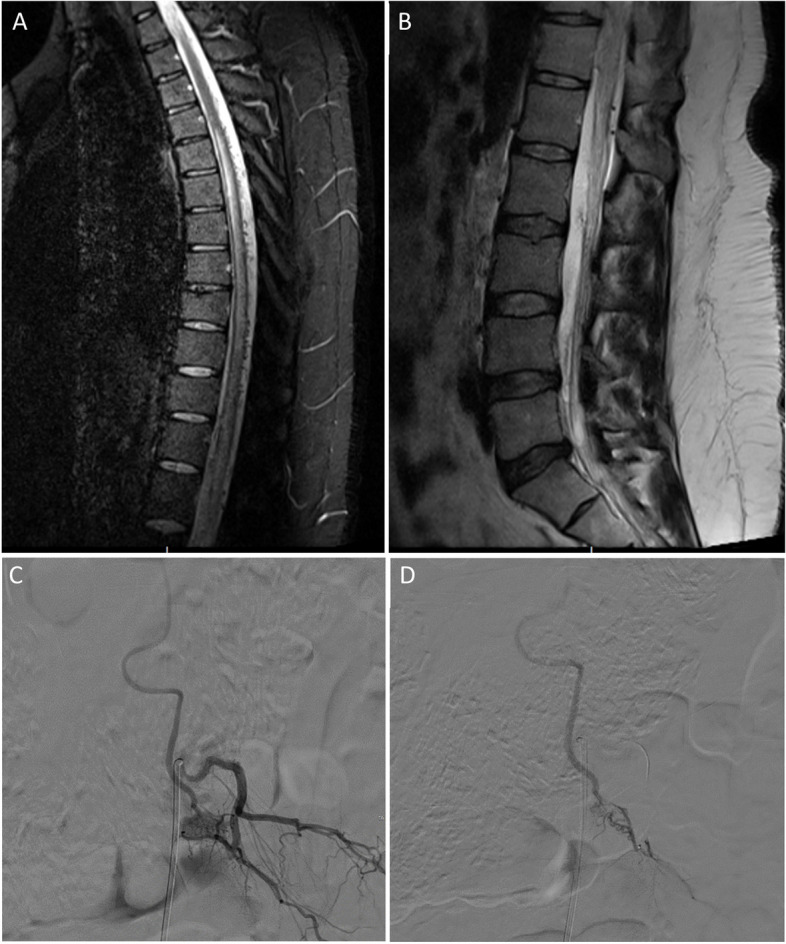

Spinal dural arteriovenous fistulas account for the majority of spinal vascular malformations. They are typically located in the thoracolumbar region and are diagnosed in the middle-aged and elderly populations. Although spinal dural arteriovenous fistulas have been postulated to be acquired, their exact development remains uncertain. Typically, the arteriovenous shunt is situated close to the spinal nerve root, inside the dura mater, where the blood from the radiculomeningeal artery and radicular vein intermix. Throughout history, there have been multiple classification systems of spinal arteriovenous shunts since 1967. Those were mainly based on the evolution of diagnostic studies as well as the treatment of these lesions. Such classification systems have undergone significant changes over the years. Unlike intracranial dural arteriovenous fistula, spinal dural arteriovenous fistula is progressive in nature. The neurological manifestations, due to venous congestion, tend to be insidious as well as non-specific. These include sensory deficits, such as paresthesia, bilateral and/or unilateral radicular pain affecting the lower limbs, and gait disturbances. Spinal dural arteriovenous fistulas can be suspected on magnetic resonance imaging/magnetic resonance angiography and confirmed by digital subtraction angiography (DSA). The management includes surgery, endovascular therapy, and in selected cases, radiotherapy. The treatment goal of spinal dural arteriovenous fistula is to halt the progression of the disease. The prognosis depends on both the duration of symptoms as well as the clinical condition prior to therapy. The present article comprehensively reviews the pathophysiology, changes in classification systems, natural history, clinical manifestations, radiological features, management, and prognosis.